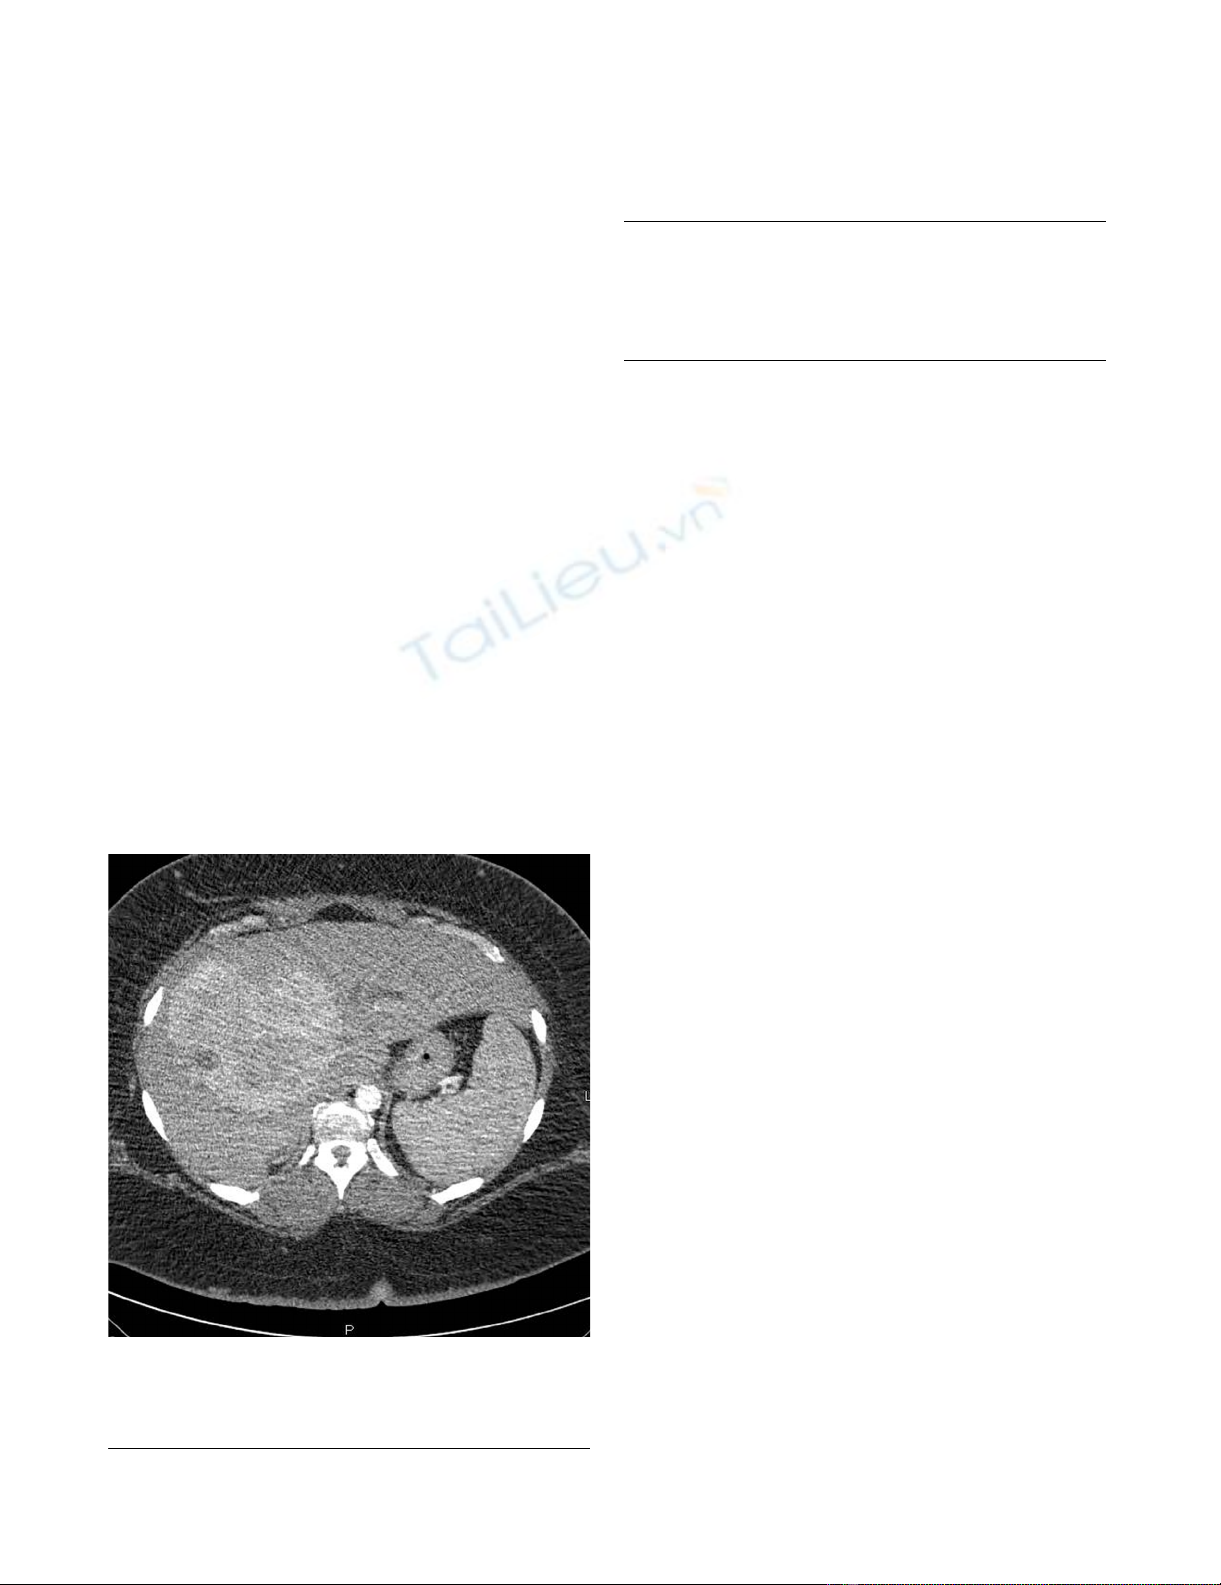

A 41-year-old woman presented with a 2-month history

mal alpha-fetoprotein (AFP) level (Table 1). A computed

tomography scan (CT-scan) revealed a large (14-cm),

hypervascular mass that involved segment IV of the left

lobe and segments V and VIII of the right lobe of the liver,

partially occluding the proximal part of the common bile

duct and causing moderate dilatation of the intrahepatic

biliary system (Figure 1). Percutaneous biopsy of the

A triple-phase helical CT scan shows a 14-cm hypervascular mass involving the right lobe and the medial segment of the left lobe of the liverFigure 1

A triple-phase helical CT scan shows a 14-cm hyper-

vascular mass involving the right lobe and the medial

segment of the left lobe of the liver.